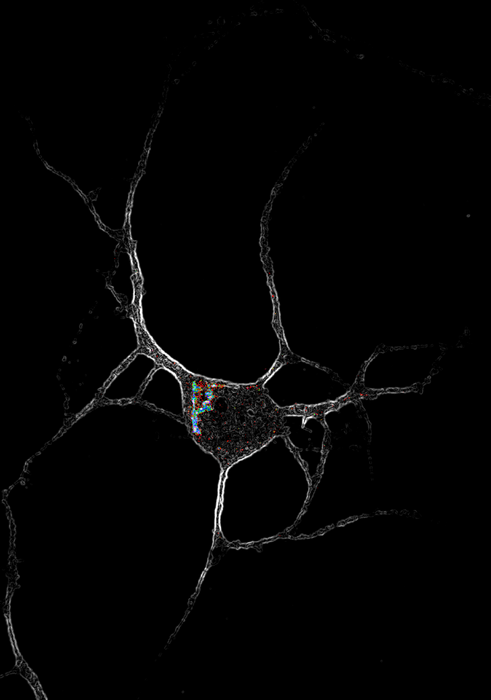

IMAGE: IMAGE OF A CORTICAL NEURON (WHITE) EXPRESSING SEROTONIN 2A (5-HT2A) RECEPTORS (MULTICOLOR). NEW WORK SHOWS THAT ENGAGING 5-HT2A RECEPTORS INSIDE CELLS, BUT NOT ON THE CELL SURFACE, ENCOURAGES CELL GROWTH AND FORMATION OF NEW CONNECTIONS. view more

CREDIT: DAVID OLSON/UC DAVIS

Location, location, location is the key for psychedelic drugs that could treat mental illness by rapidly rebuilding connections between nerve cells. In a paper published Feb. 17 in Science, researchers at the University of California, Davis show that engaging serotonin 2A receptors inside neurons promotes growth of new connections but engaging the same receptor on the surface of nerve cells does not.

Drug receptors are usually thought of as being on the cell membrane, facing out. But the researchers found that in nerve cells, serotonin 2A receptors were concentrated inside cells, mostly around a structure called the Golgi body, with some receptors on the cell surface. Other types of signaling receptors in the same class were on the surface.

The results show that there is a location bias in how these drugs work, Olson said. Engaging the serotonin 2A receptor when it is inside a cell produces a different effect from triggering it when it is on the outside.